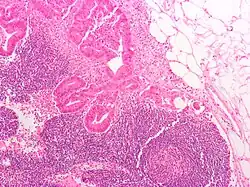

Adenocarcinoma invasivo (o tipo mais comum de cancro colorretal). Células cancerosas estão no centro e à esquerda inferior da imagem (em azul).

O tipo do tumor é geralmente diagnosticado através da análise de tecido removido através de uma biópsia ou cirurgia. O diagnóstico patológico geralmente contém a descrição histológica do cancro, e o grau. O tipo mais comum de cancro colorretal é adenocarcinoma, que compõe 95% dos casos - acredita-se que a maioria dos casos de cancro colorretal envolvam tumores originários de pólipos adematosos. Outros tipos, mais raros, de cancro colorretal, incluem linfoma e carcinoma espinocelular. As causas do cancro colorretal não são conhecidas com exatidão no presente.

Adenocarcinoma é um tipo de tumor maligno epitelial, que se origina do epitélio glandular da mucosa colorretal. Tal tumor invade a parede, infiltrando a mucosa muscular, a submucosa, e daí, a muscularis propria. As células do tumor abrigam estruturas tubulares irregulares, de estrutura pluristratificada, lúmens múltiplos, e estromas reduzidos. Por vezes, as células do tumor secretam muco, que invade o fluido intersticial, produzindo grandes agrupamentos de muco e colóide (que, visualmente, aparecem como "espaços vazios") - é o chamado adenocarcinoma colóide, pouco diferenciado. Se o muco permanece dentro da célula do tumor, o muco empurra o núcleo celular para a periferia da célula - célula do tipo signet-ring. Dependendo da arquitetura glaudular, pleomorfismo celular, e padrão da secreção de muco, o adenocarcinoma pode ser categorizado em três graus de diferenciação: bem diferenciado, moderadamente diferenciado, e mal diferenciado.[48]